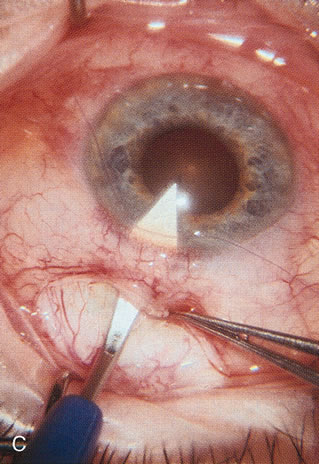

Fig. 1. The anatomic advantage of small incision cataract surgery for the glaucoma patient. A. Long-term bleb function with a large cataract incision is difficult to achieve with either ECCE-trabeculectomy or trabeculectomy followed later by ECCE. This bleb failed to form sufficiently when combined with large incision ECCE. The inflammation, bleeding, and long-term wound healing with stimulation of fibroblasts associated with this technique are more likely to cause bleb failure. In addition, the increased iris manipulation necessary to deliver the nucleus and subsequent iris repair adds to the long-term breakdown of the blood aqueous barrier. B and C. Two-site phacotrabeculectomy has the advantage of small incision cataract surgery combined with separate site trabeculectomy. The incision size is one third the size of the standard ECCE. The inflammation is less severe, and cataract wound healing is confined to the temporal area. Visual rehabilitation with phacoemulsification and foldable IOL is much faster. Phacoemulsification allows successful lens extraction even in the unfriendly environment of a smaller pupil compared with ECCE. The trabeculectomy is performed in an entirely different site, well away from the wound healing associated with temporal phacoemulsification. The likelihood of this filter functioning long-term is greater than with ECCE-trabeculectomy. D. The surgeon also has the option of single-site phacotrabeculectomy with foldable IOL. Both the lens extraction and trabeculectomy are performed through one small 3.5-mm limbal incision.

Fig. 3. Partial bleb failure following clear corneal phacoemulsification with foldable IOL. A. Preoperative bleb appearance prior to temporal lens extraction. Preoperative IOP was 12 mm Hg on no antiglaucoma medications. Time from 5-FU trabeculectomy surgery to lens extraction was one year. B. Bleb appearance 2 months after clear corneal cataract surgery with topical anesthesia. Following lens extraction, increased vascularity was noted along with decreased size of the filtering bleb. IOP increased to 20 mm Hg as early as 2 weeks after surgery, necessitating topical antiglaucoma therapy. C. High magnification view of bleb before lens extraction demonstrates diffuse pale bleb. D. High magnification view of bleb 2 months after surgery. There are vessels surrounding the nasal side of the bleb and the overall bleb size is smaller.